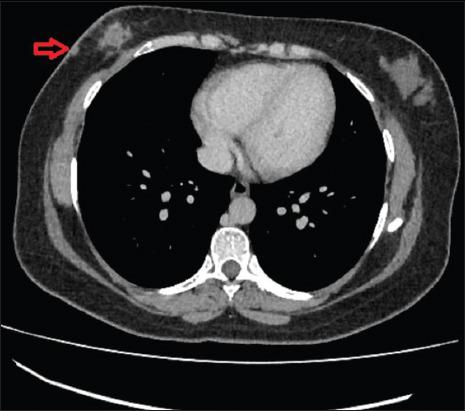

A total of eight cases were identified, out of which seven were females. The most common presentation consisted of the presence of metastatic nodules which were seen in 62.5% (five out of eight) of the patients. Other features consisted of erythematous or plaque-like skin thickening on clinical examination, increased density with indistinct margins seen on a mammogram and diffuse oedematous changes in the skin with small irregular mass or infiltration into subcutaneous tissues were visualised on ultrasound and CT studies.